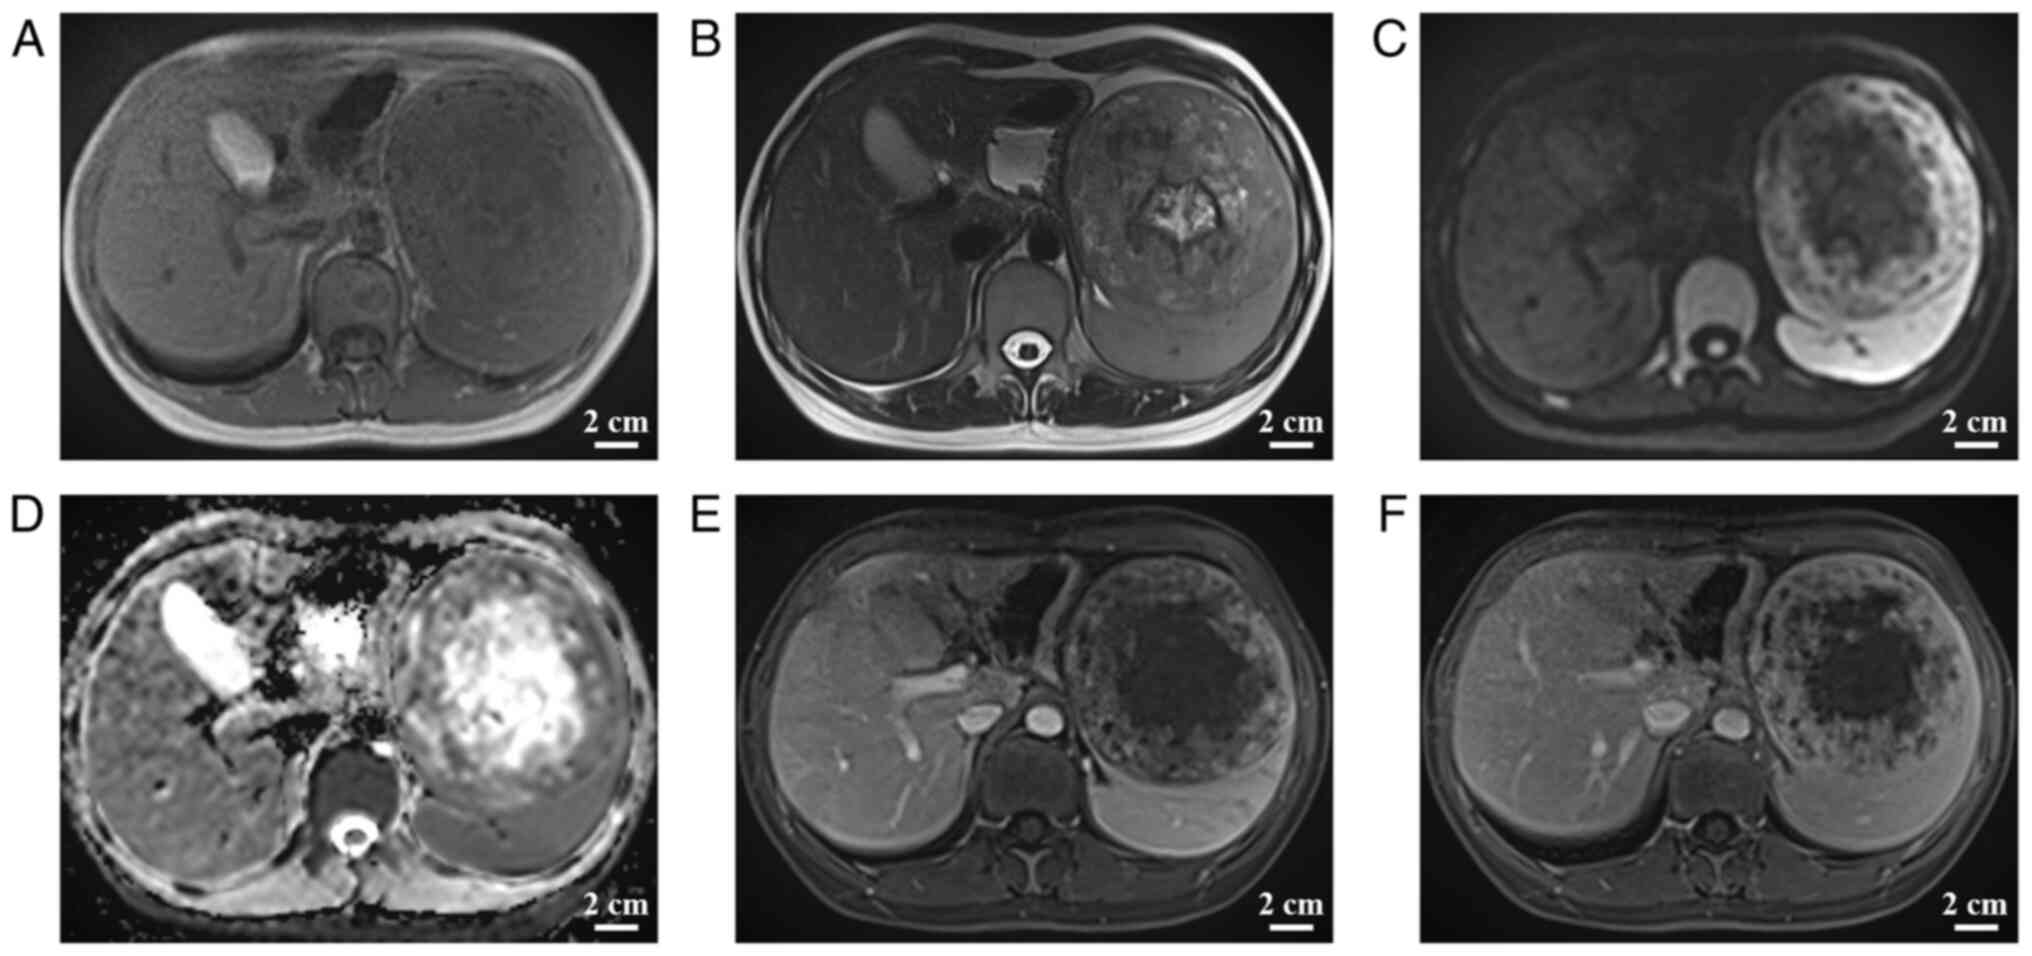

A 29-year-old female patient presented at the First People's Hospital of Zunyi (Guizhou, China) in July 2021, where a large splenic mass was incidentally detected during an abdominal ultrasound examination for their company-required annual physical examination. Physical examination revealed mild tenderness to palpation in the left upper quadrant. The levels of the tumor markers α-fetoprotein, carcinoembryonic antigen, carbohydrate antigen 125 (CA125) and CA199 were all normal. The patient denied having any remarkable medical personal or family history. Abdominal sonography revealed a heterogeneous echogenic mass measuring ~12.8×11.4×12.1 cm with hazy borders and poorly defined surrounding tissue. There was a fluid hypoechoic region within the mass, as well as dotted and streaked blood hyposignals in and around the mass (Fig. 1).

Figure 1.

On day 2 after hospitalization, abdominal ultrasonography showed a mixed echogenic mass in the spleen, which is poorly demarcated from the spleen parenchyma, with uneven internal echogenicity and liquid dark areas within the mass; color Doppler ultrasound indicates dotted streaks of blood hypo-signal around the mass (scale bar, 2 cm).